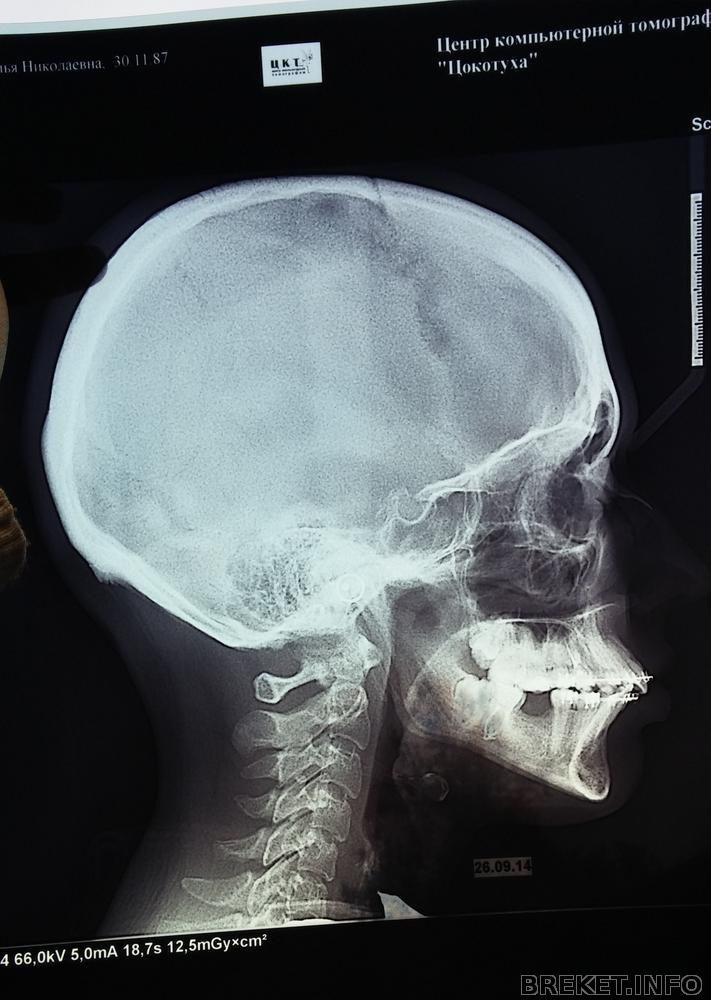

Тяжкий путь брекетоносца (внутри черепушка в профиль)

Срок брекетоношения близится к отметке "год". Но новости безрадостные, чувствую не скоро это закончится. Побывала ещё у одного ортодонта. На этот раз это был проверенный профессионал своего дела. Ну естественно мне сказали об удалении 4ок, в последствии и 8ок(чтоб не было рецидива после лечения). Подтвердили о том, что на единице брекет наклеен не правильно, от того и криво стоит зуб. Я всё это знала и сама..нужно было профессиональное подтверждение, почти за 3000т.р (снимки+консультация) я это подтверждение получила. Надо заметить, после снимка в профиль я была в шоке. Дистальный прикус ужасен. И мой нынешний ортодонт через месяц собирается снимать брекеты. Считает, что всё отлично. Фото прилагаю: